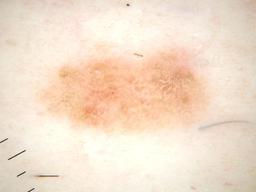

{

"age_approx": 30,

"anatom_site_general": "anterior torso",

"clin_size_long_diam_mm": "3.00",

"concomitant_biopsy": false,

"diagnosis_1": "Benign",

"diagnosis_2": "Benign melanocytic proliferations",

"diagnosis_3": "Nevus",

"diagnosis_4": "Nevus, Atypical, Dysplastic, or Clark",

"diagnosis_5": "Nevus, Clark",

"diagnosis_confirm_type": "single image expert consensus",

"family_hx_mm": false,

"image_type": "dermoscopic",

"melanocytic": true,

"personal_hx_mm": false,

"sex": "female"

}